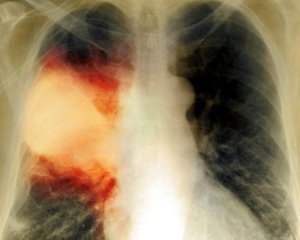

Троє пацієнтів міської лікарні Тернополя померли від вірусної пневмонії. П'ятеро перебувають із цим захворюванням в реанімації.

Лікарі наполягають на звертанні до них у перший день високої температури. Якщо за три дні не спадає, то призначать рентген, який виявить пневмонію.